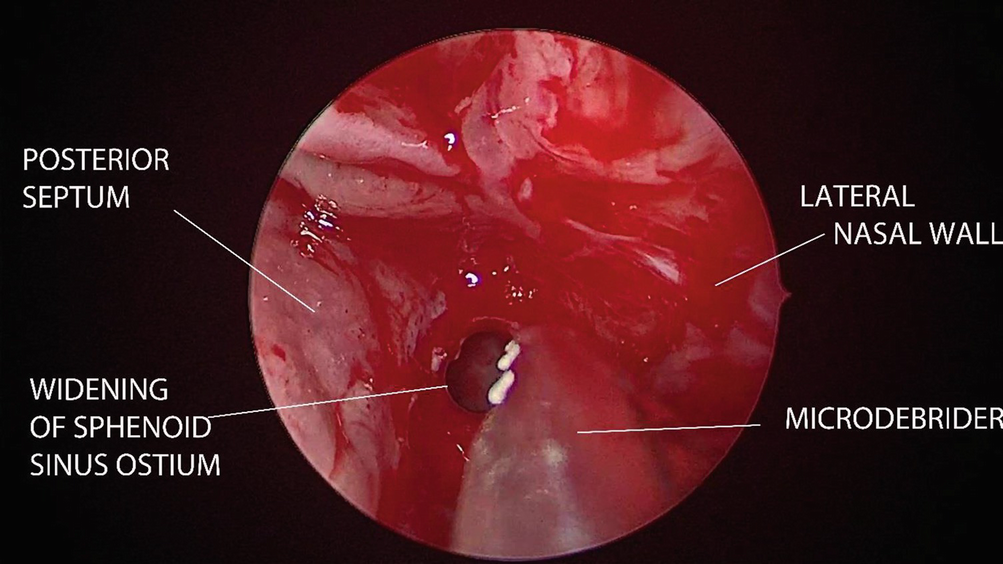

The sphenoid sinus is entered as inferiorly and medially as possible from the posterior ethmoid cell if a transethmoid sphenoidotomy is being done. The sphenoid ostium can also be identified by blunt probing 1.5 cm from the posterior choanae or by excising a small inferior part of superior turbinate when a transnasal sphenoidotomy is being done. When clearing the sphenoid sinuses of disease, the carotid artery and optic nerve located on both of its lateral wall must be kept in mind (Fig. 12.5).

../images/481431_1_En_12_Chapter/481431_1_En_12_Fig5_HTML.png

Fig. 12.5

Sphenoidotomy is done by using a microdebrider